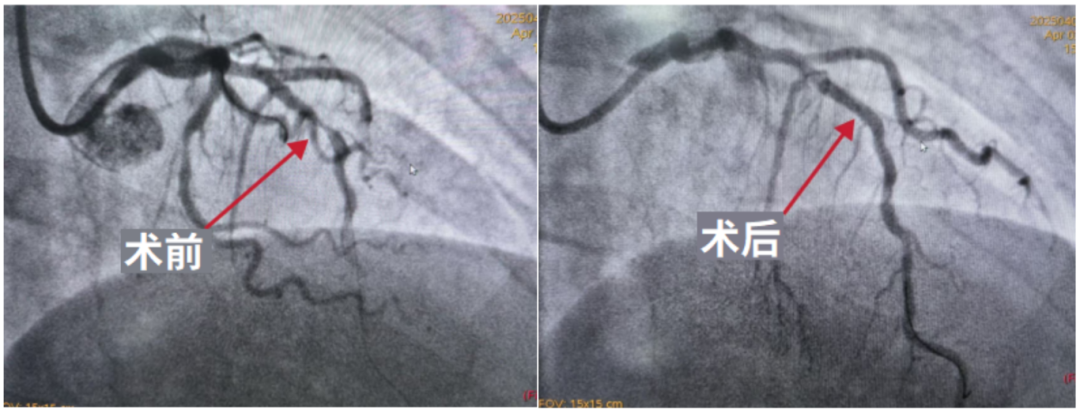

行PCI术,于前降支中段狭窄病变处植入2.75*14mm药物支架。

本例患者为中老年女性,确诊冠心病(前降支中段狭窄90%),合并高血压、高脂血症、肥胖等多重心血管代谢危险因素,同时伴有脂肪肝、胆囊炎并胆囊结石。此类多病共存患者远期心血管事件风险显著增高,预后较差。基于此,主管医师采取了“急慢分治、综合管理”策略:一方面针对冠脉严重狭窄病变及时行PCI术,通过血运重建快速解除缺血症状;另一方面,对多重心血管代谢危险因素进行综合管理,从源头降低动脉粥样硬化风险,改善患者远期预后。